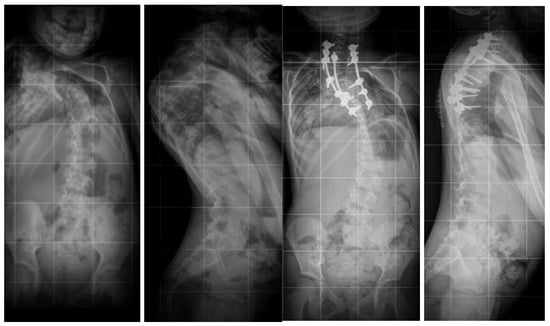

- Grabala, P.; Fani, N.; Gregorczyk, J.; Grabala, M. Posterior-only T11 vertebral column resection for pediatric congenital kyphosis surgical correction. Medicina 2024, 60, 897. [Google Scholar] [CrossRef] [PubMed]